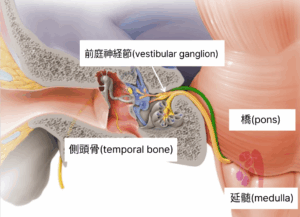

前庭神経炎とは、突然激しいめまいを感じ、吐き気、むかつき、嘔気を伴い、バランスを取ることが困難になる疾患です。前庭神経の炎症により発生すると知られていますが、原因が明確に解明されているわけではありません。対症的な薬物治療で回復を期待しますが、めまいや随伴症状が完全に消失せず、持続的に現れる場合が多いのです。

果たして前庭神経炎とめまいは寛解が困難な疾患なのでしょうか?